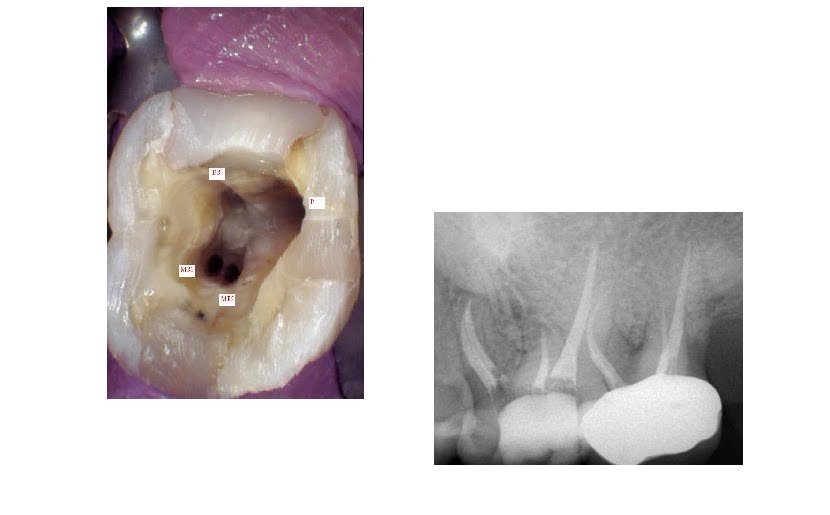

Endodontic treatment of the maxillary first molar with five root canals What Endodontic Procedure Is Performed On A Primary Molar While endodontists perform only 25% of the total root canal. the basic differences between primary and permanent root canal anatomy. a root canal is treatment for infections in tooth pulp, the innermost layer of your teeth. Fear is a tremendous influence on the perception of pain. Choose a link below to learn. — endodontic management of primary. What Endodontic Procedure Is Performed On A Primary Molar.